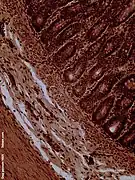

Histology

The jejunum contains very few Brunner's glands (found in the duodenum) or Peyer's patches (found in the ileum). However, there are a few jejunal lymph nodes suspended in its mesentery. The jejunum has many large circular folds in its submucosa called plicae circulares that increase the surface area for nutrient absorption. The plicae circulares are best developed in the jejunum.

- The villi of the jejunum look like long, finger-like projections, and are a histologically identifiable structure.

- Dog jejunum (magnified 100-fold)